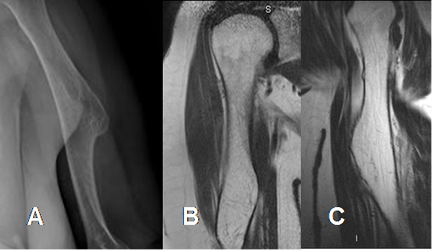

Fig 77. Osteocondroma.

A: Rx AP, B: RM coronal en T1 y C: RM sagital en T1. Exostosis del húmero con continuidad de la medular osea, por osteocondroma.